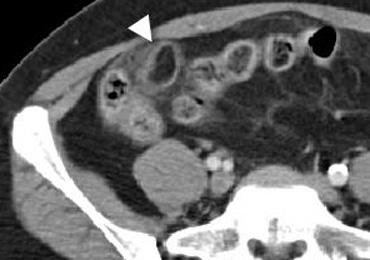

CT điển hình của viêm mấu nối mạc nối với khối mỡ bên phải được bao quanh bởi một vòng tăng tỷ trọng.

Viêm mấu nối mạc nối.

Các mấu nối mạc nối là những phần nhô ra nhỏ chứa mô mỡ từ bề mặt thanh mạc của đại tràng.

Một mấu nối mạc nối có thể bị xoắn và viêm thứ phát gây đau bụng khu trú, bắt chước viêm ruột thừa khi nằm ở hố chậu phải hoặc bắt chước viêm túi thừa khi nằm ở hố chậu trái.

Dấu hiệu vòng đặc trưng tương ứng với lớp phúc mạc tạng bị viêm bao quanh một mấu nối mạc nối bị nhồi máu.

Viêm mấu nối mạc nối bên trái ở bệnh nhân nghi ngờ lâm sàng là viêm túi thừa. Dấu hiệu vòng tăng tỷ trọng đặc trưng.

Viêm mấu nối mạc nối đã được ghi nhận ở khoảng 1% bệnh nhân nghi ngờ lâm sàng là viêm ruột thừa.

Việc chẩn đoán xác định thực thể đặc trưng này là rất quan trọng vì viêm mấu nối mạc nối là bệnh tự giới hạn.

Cả siêu âm và CT đều có thể phát hiện khối mỡ bị viêm nằm kề cạnh đại tràng.

Dấu hiệu chính: Khối mỡ bị viêm nằm kề cạnh đại tràng với dấu hiệu vòng đặc trưng.